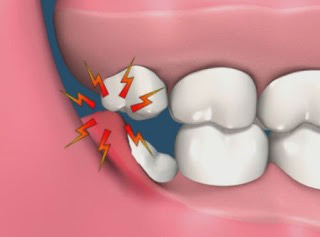

一般来说,如果智齿反复肿痛

或智齿对侧没有对象,发生了过度萌生现象

甚至直接咬到对侧牙龈

亦或经常食物嵌塞,清洁不到位,口腔内会出现异味

更甚者,可能导致颞下颌关节紊乱

总之,这些智齿就是要和你来个鱼死网破

不拔,难道等着过年吗?